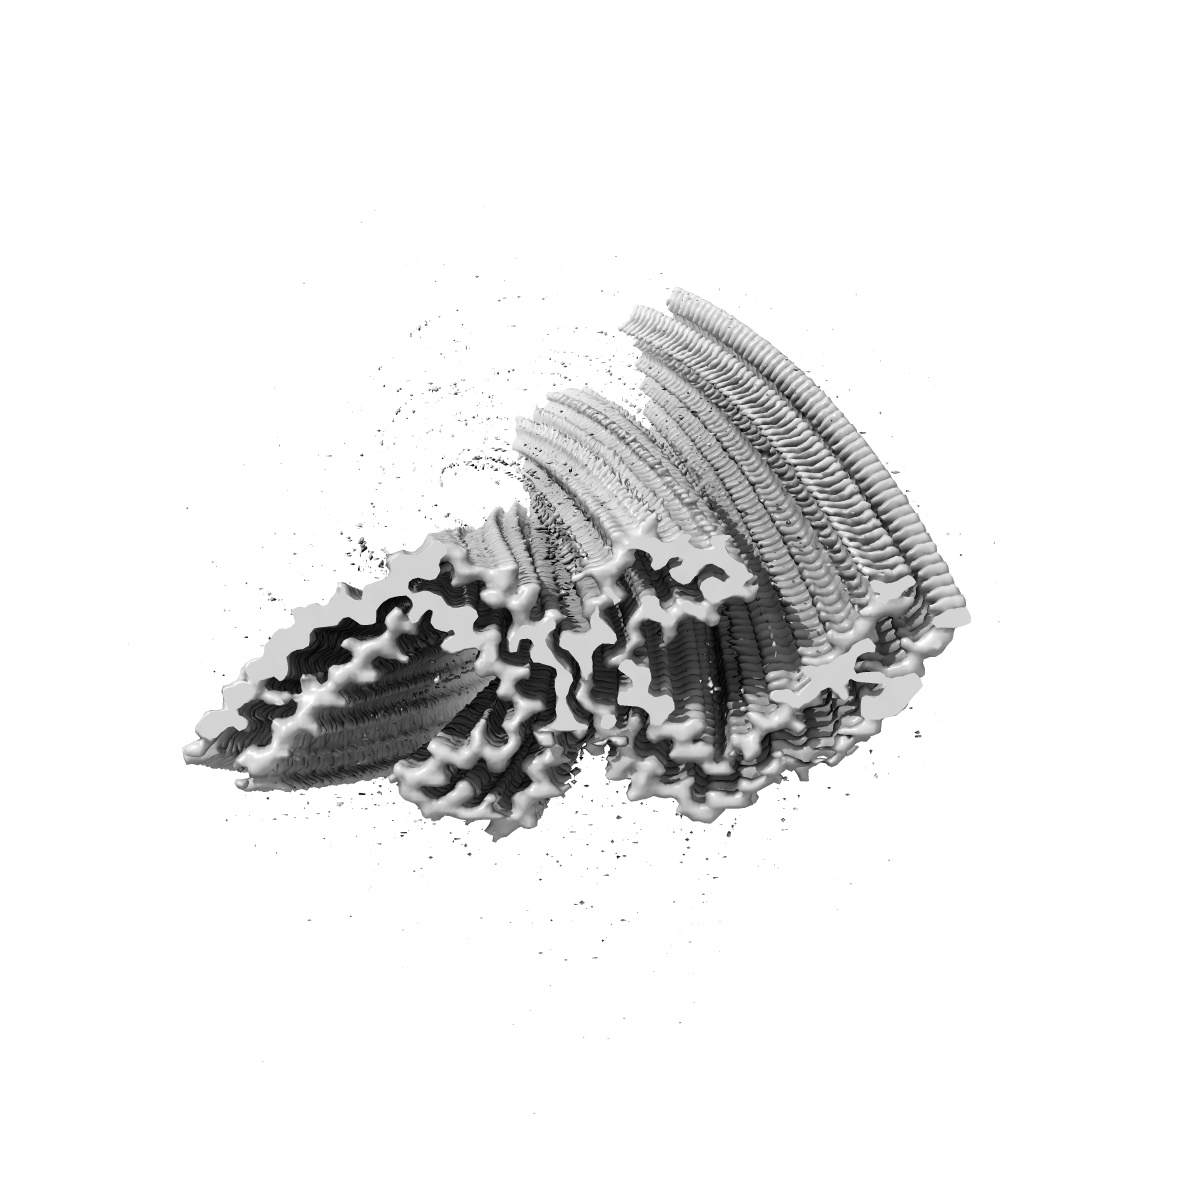

Paired helical filament from sporadic Alzheimer's disease brain

Sample: Tau filaments extracted from the frontotemporal cortex of a patient with sporadic Alzheimer's disease

Tau filaments from multiple cases of sporadic and inherited Alzheimer's disease adopt a common fold.

Falcon B, Zhang W , Schweighauser M , Murzin AG, Vidal R , Garringer HJ , Ghetti B , Scheres SHW , Goedert M

(2018) Acta Neuropathol , 136 , 699 - 708